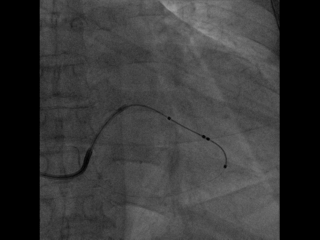

尝试抓捕器在右房抓捕runthough导丝成功,并进行牵拉

非常幸运,通过抓捕器的牵引力,电极顺利通过狭窄处,确定电极固定牢靠,抓捕器释放导丝并撤出,初步测试左室阈值满意,没有PNS。